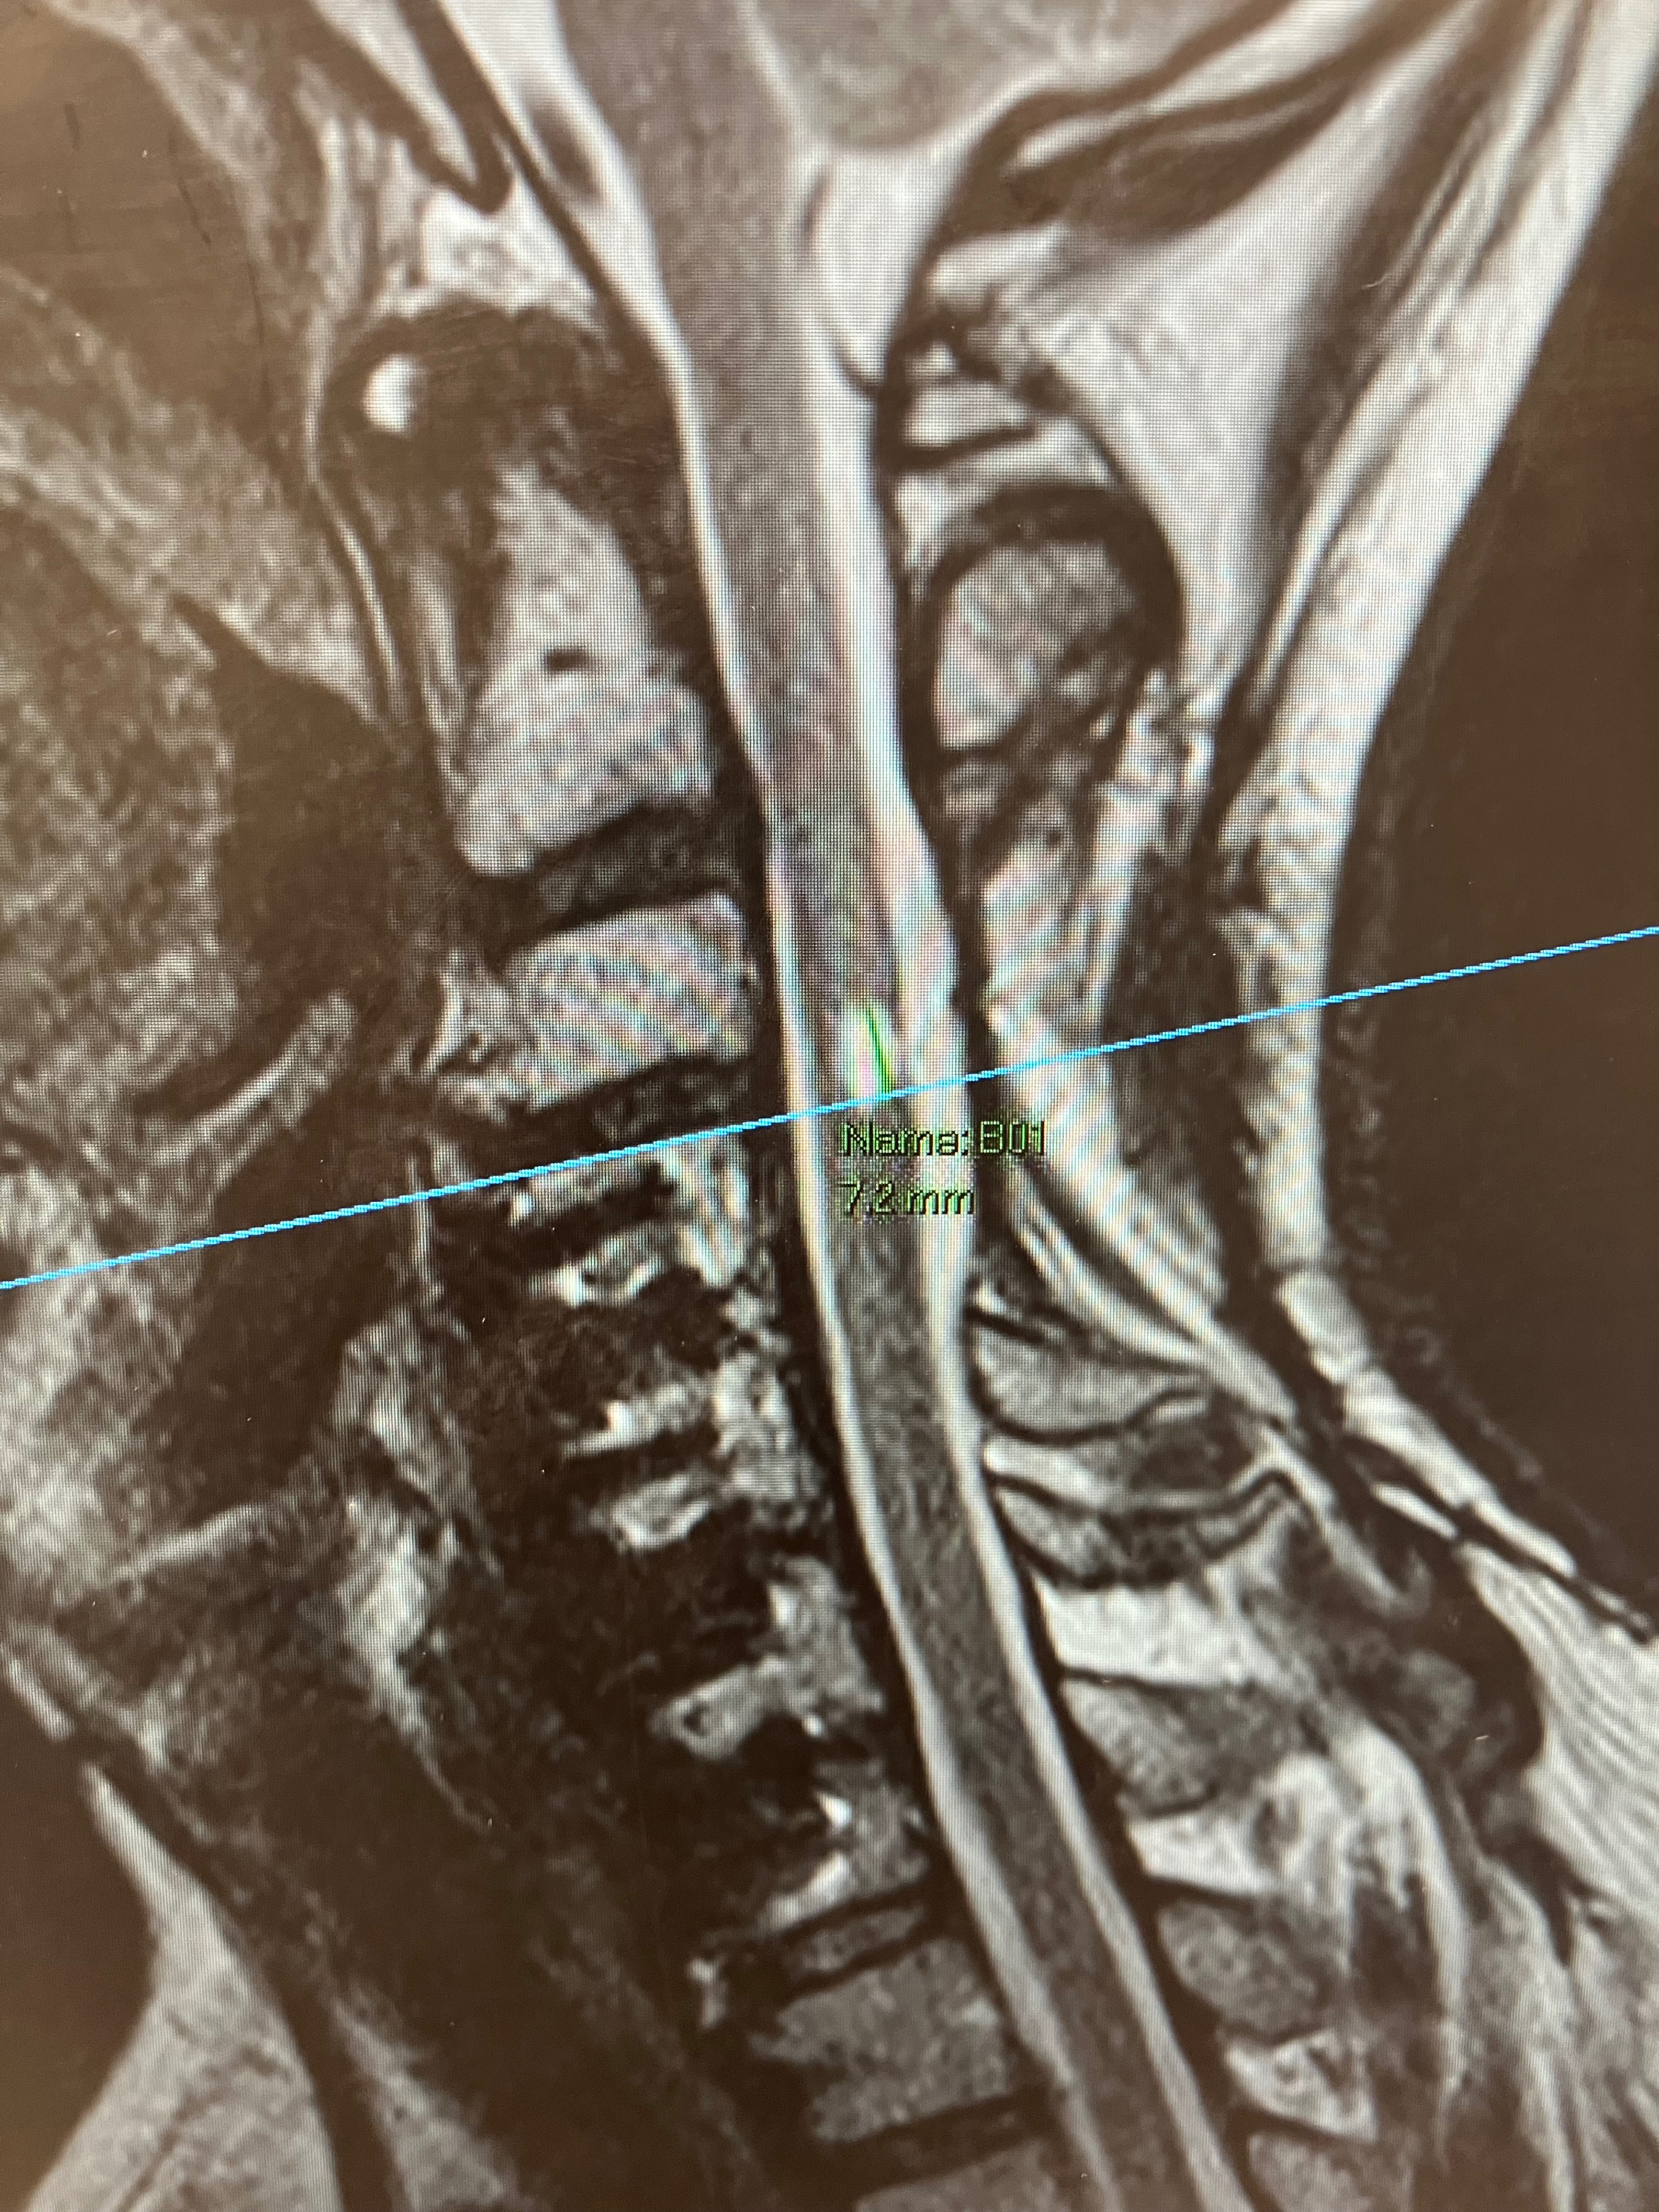

While I’ve made progress, I’m still facing total body numbness and serious nerve damage. I suffer daily from constant burning, tingling, and electric-like pain caused by a 9mm bump on my spinal cord blocking all the signals to reach my brain. Doctors say the only real solution is advanced spinal cord surgery and stem cell treatment not covered by insurance.